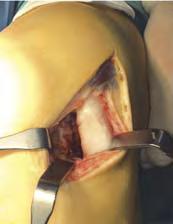

Leczenie operacyjne

Zabiegi naprawcze